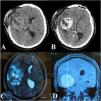

Solitary fibrous tumors (SFTs) are rare intracranial neoplasms that are highly vascular, making surgical resection challenging due to significant intraoperative blood loss. Preoperative embolization is commonly performed via the transarterial route; however, this approach has limitations, including difficulty in accessing multiple feeders, prolonged procedural time, and the risk of embolic material reflux into the intracranial circulation.

Here, we report the case of a 19-year-old male with a large intracranial SFT, initially treated with transarterial embolization using polyvinyl alcohol (PVA) particles, which failed to achieve proper devascularization of the tumor. Consequently, direct puncture embolization using the SQUID 12 agent was performed. Following successful embolization, complete tumor resection was achieved with significantly reduced intraoperative blood loss and no postoperative neurological deficits.

This case highlights the effectiveness of direct puncture embolization as a viable alternative to traditional transarterial approaches for managing highly vascular intracranial tumors.